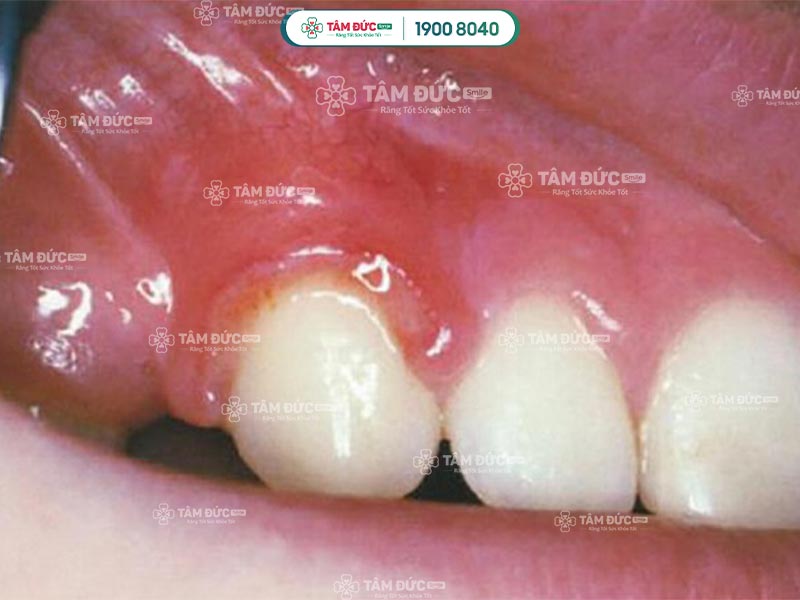

Viêm nướu chân răng do bị chấn thương

Viêm nướu chân răng ở giai đoạn này nếu phát hiện sớm sẽ dễ điều trị. Quý khách có thể nhận biết viêm nướu răng qua các dấu hiệu sau:

- Nướu đau, sưng to và chuyển thành màu đỏ thẫm.

- Chảy máu xung quanh chân, kẽ răng.

- Hơi thở có mùi hôi khó chịu.

Viêm nướu chân răng làm gây tụt lợi